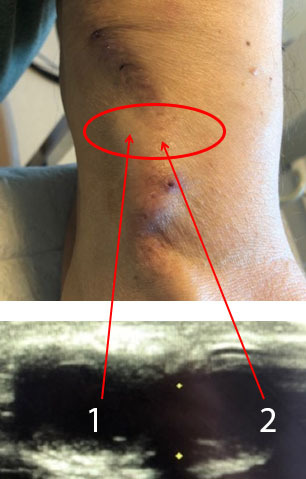

Dialysis Pseudoaneurysm Graphic and Image

Pseudoaneurysm

Graft